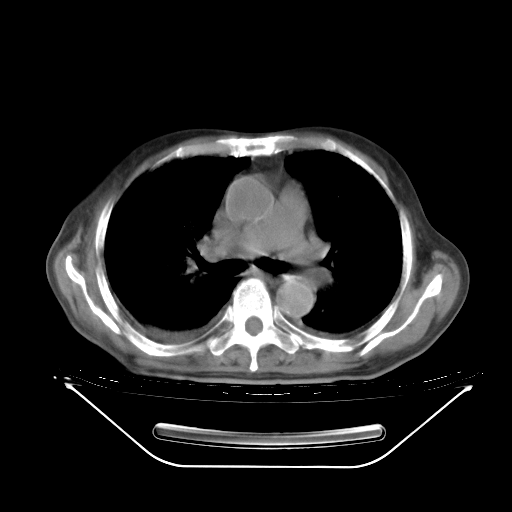

今天复查肺部CT,发现双肺广泛磨玻璃样改变。所以我把3月19日和5月9日相隔50天的肺部CT上传。请大家会诊。

2009年3月19日肺部CT片。

5月9日肺部CT(在4月27日齐鲁医院肺部CT描述部分肺组织磨玻璃样改变,12天后肺组织广泛磨玻璃样改变)